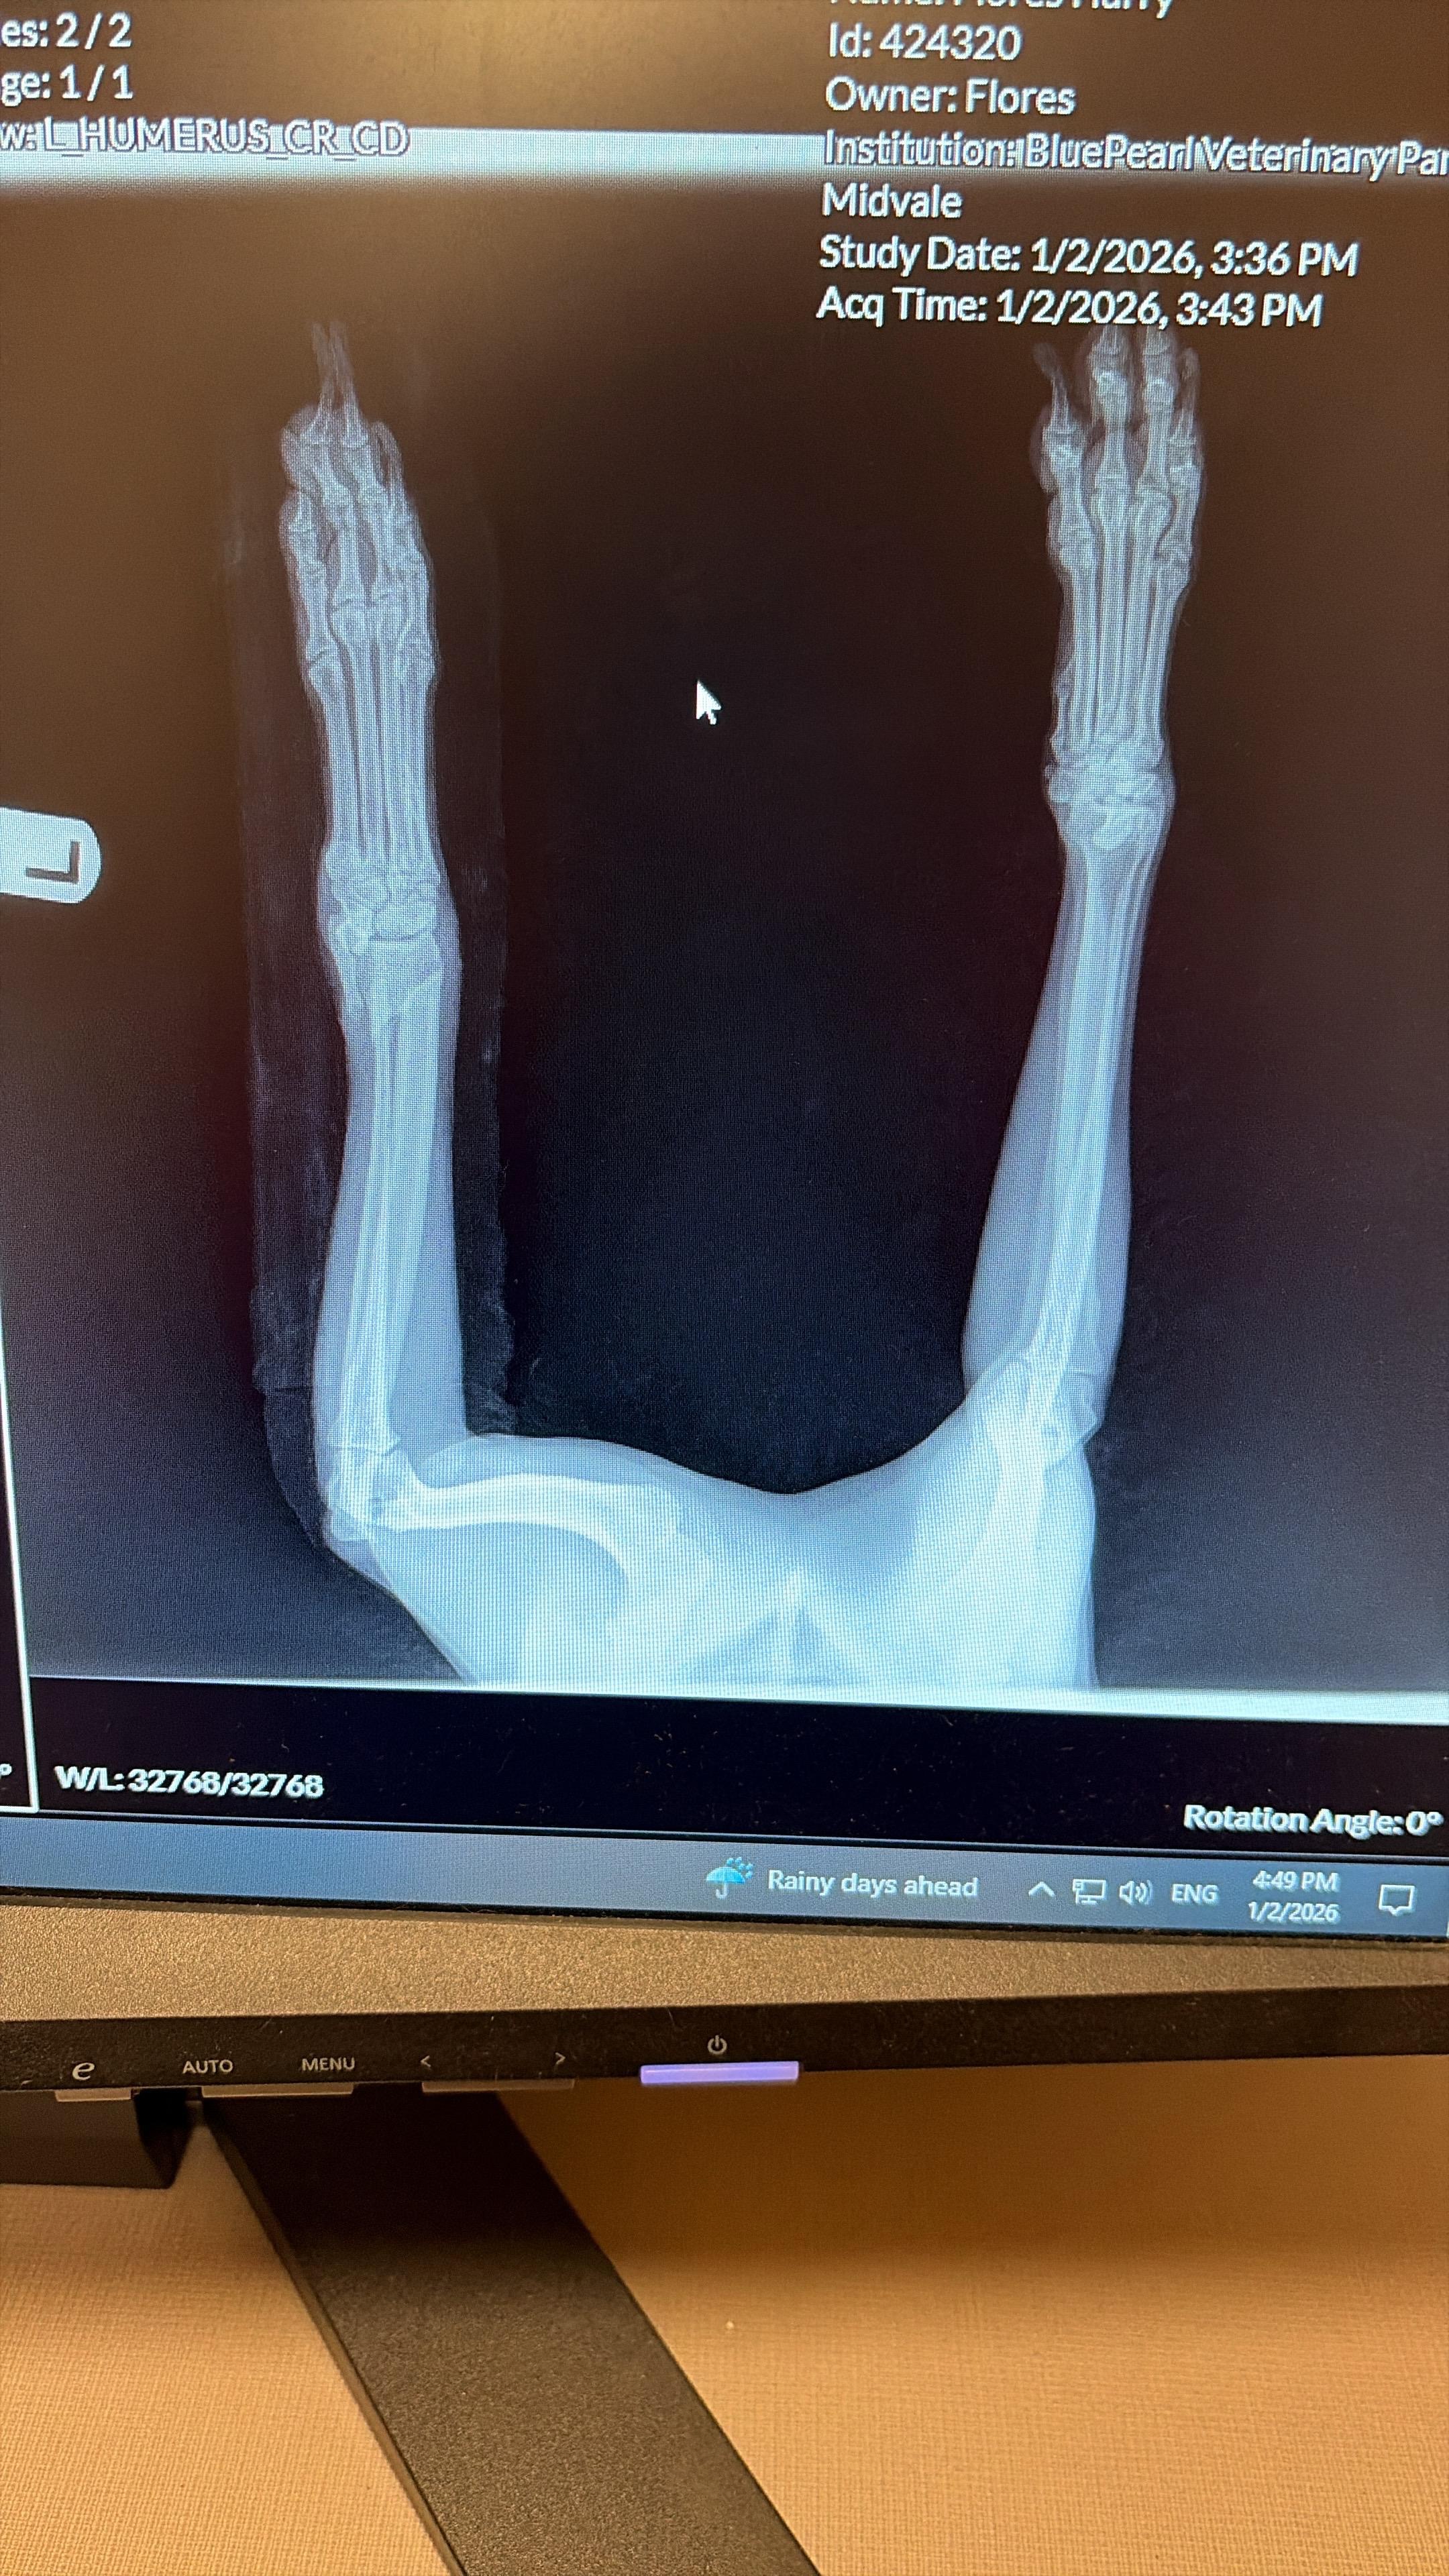

Our dog Harry, a 4-year-old Goldendoodle, was recently injured and rushed to an emergency veterinary hospital. He has fractures in both bones of his front leg (the radius and ulna). Unfortunately, the breaks are displaced, meaning the bones are not lined up correctly and will not heal on their own.

To prevent further damage and reduce his pain, the veterinary team placed a temporary splint and started him on pain medication and antibiotics. However, this is only a short-term solution. Harry urgently needs orthopedic surgery to properly repair the fractures and avoid serious complications, long-term pain, or loss of function in his leg.